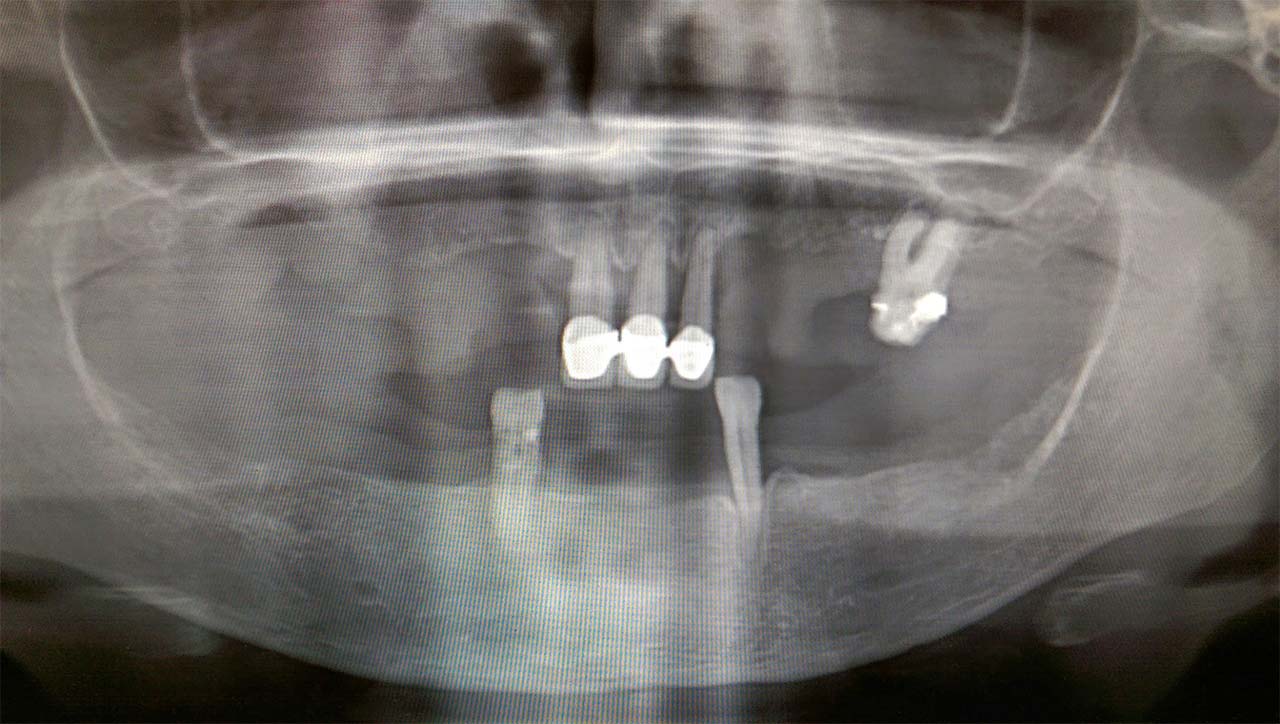

Alsó állcsont teljes rehabilitációja 72 óra alatt

Alsó állcsont teljes rehabilitációja 72 óra alatt, azonnal terhelhető implantátumokkal súlyos paradontitisben szenvedő dohányzó páciens esetében. Az alsó állcsont fogai mind mozogtak az előrehaladott fogágypusztulás miatt.

A fogakat eltávolítottuk, a gyulladt, fertőzött csontot kitakarítottuk, kifertőtlenítettük, majd azonnal implantáltunk.

Svájci, IHDE márkájú, azonnal terhelhető implantátumokat helyzetünk be, és ezekre harmadnapra rögzített, hosszútávú, fémvázas, esztétikus műanyaggal leplezett hidat ragasztottunk be.

Ezt az ideiglenes hidat a sebek gyógyulása miatt használjuk, de tartóssága miatt véglegesként is használható. A legtöbb esetben, ahogy itt is, 6 hónap múlva porcelán hídra cseréljük, a teljes gyógyulás után.